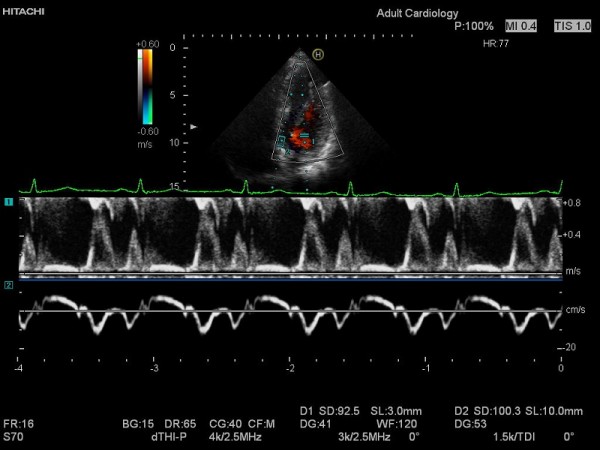

- BAREVNÝ A ENERGETICKÝ DOPPLER

- TDI

- PW

- M-MODE